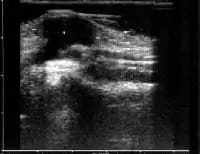

На приведенном ниже ультразвуковом изображении показана киста ганглия (область между маркерами).

- Ваш врач может получить дополнительное подтверждение, используя шприц, чтобы вытянуть часть жидкости из кисты (аспирация иглой) или с помощью ультразвука. Ультразвуковая картина создается по мере того, как звуковые волны отражаются от различных тканей. Он может определить, заполнена ли опухоль жидкостью (кистозная) или твердая. Ультразвук также может определить, есть ли артерия или кровеносный сосуд, вызывающие опухоль.